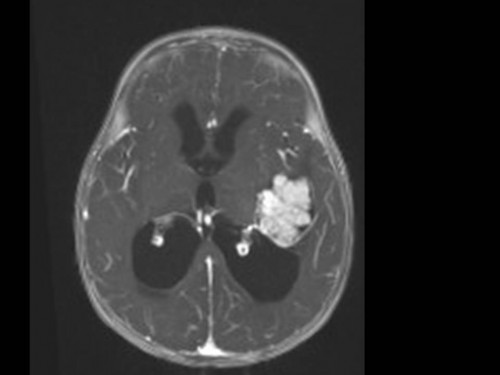

10 Monate altes Mädchen. Der Kinderarzt stellt fest, dass das kleine Mädchen einen recht großen Kopfumfang hat, nicht mit den Augen fixiert und anscheinend auch nicht richtig sehen kann. Damit bestätigt er die größten Befürchtungen der Eltern, denen in den letzten Wochen aufgefallen war, dass ihre Tochter nach keinem Spielzeug mehr greift und sie nur dann anlächelt, wenn sie zu ihr sprechen.

Bildgebung - MRT